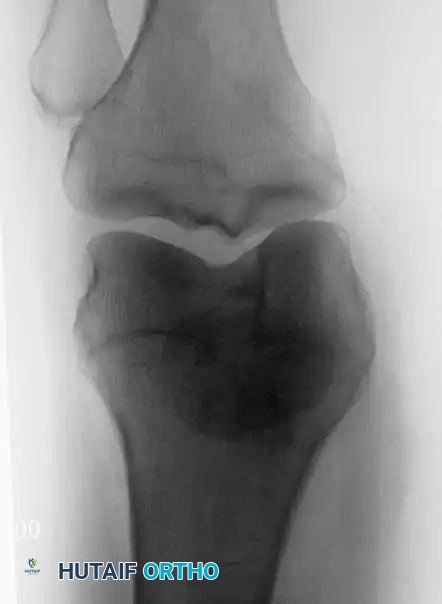

Anteroposterior radiograph of the right humerus in a 36-year-old man with primary lymphoma of bone. Note the extensive permeative bone destruction and cortical thinning. Despite this massive structural compromise, the patient’s symptoms were surprisingly mild.

Radiographically, lymphoma typically presents as an ill-defined area of bone destruction. It exhibits a predilection for the diaphyseal or metadiaphyseal regions of long bones. The classic appearance is a "permeative" or "moth-eaten" pattern of osteolysis, indicative of a rapidly infiltrating round cell tumor.

While the cortex may appear thickened due to chronic endosteal scalloping and reactive bone formation, a florid periosteal reaction is rarely observed unless a pathological microfracture has occurred. Frequently, a massive segment of the bone—or even the entire diaphysis—is involved.